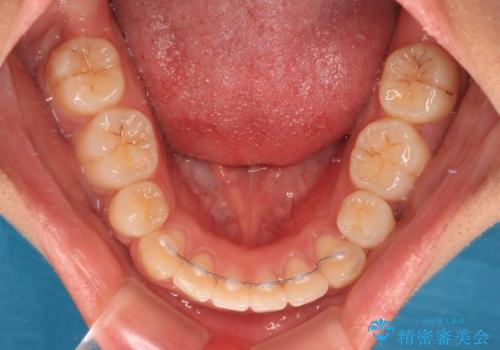

舌の突出癖により上下前歯は非接触であり、非常に前方に飛び出している状態でした。

舌のトレーニングをしっかりと行っていただき、口の閉じやすい歯並びに仕上げることができました。